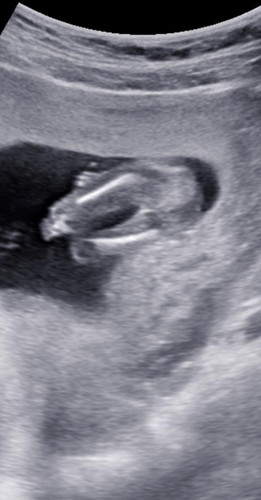

ภาพนี้ซาวด์ตอน15วีคค่ะ แต่ไม่เห็นอะไรเลย ลูกคนแรกตื่นเต้นและลุ้นมากๆค่ะ แม่ๆทราบเพศน้องกันตอนกี่วีคคะ

ถ้าภาพนี้เป็นช่วงเสยก้นน้อง.. น่าจะเป็นลูกสาวนะคะ 🙂

ดูจากภาพแล้วน่าจะเป็นผญค่ะ😅

จากภาพซาวด์ .. ผญ แน่นอนค่ะ